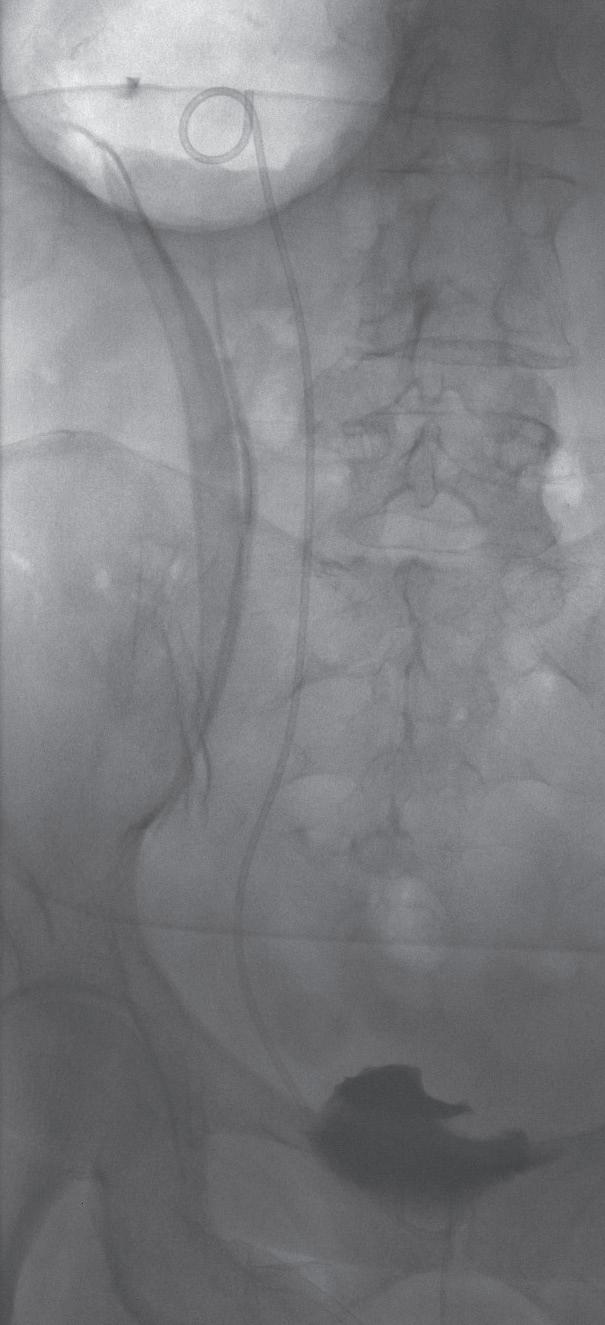

Miniperc 1: Kontrastmitteldarstellung der Kelche und des Nierenbeckens sowie Punktion.

Miniperc 2: Zugang mittels Einschrittdilatators.

Miniperc 3: Finales Bild mit antegrader DJ-Anlage.

Zeigt sich eine ausgeprägte Nephrolithiasis mit einer Größe von über 2 cm, so ist eine PCNL (perkutane Nephrolitholapaxie) empfehlenswert. Diese wird in der Regel mit rigiden Endoskopen durchgeführt und erlebte in den letzten Jahren eine sehr positive Entwicklung. Während in der Vergangenheit klassischerweise Endoskope mit einem Durchmesser von 20 Charrière (Ch.) und Zugangsschäfte von 24-32 Ch. zum Einsatz kamen, hat die zunehmende Verfügbarkeit von miniaturisierten Instrumenten dazu geführt, dass auch größere Steine in der Niere minimalinvasiv bei kürzeren stationären Aufenthalten als früher behandelt werden können. Die PCNL ist deshalb heute kein allgemeingültiger Standard mehr, sondern wird durch die Mini-PCNL, UltraminiPCNL oder Mikro-PCNL verdrängt. Mini-, Ultramini- und Mikro- beziehen sich dabei auf die durchschnittliche Größe der Instrumente. Je kleiner der Durchmesser der Geräte ist, desto geringer das Trauma und somit auch das Blu-

tungsrisiko. Ein kleinerer Durchmesser bedeutet aber auch längere OP-Zeiten. Grundsätzlich wird der Zugang durch die Haut mittels einer entsprechenden Nierenpunktion gelegt (siehe Abbildung, S. 23). Die exakte Positionierung der Punktionsstelle sollte mittels Punktionssonografie und idealerweise kombiniert mit einer Röntgendurchleuchtung erfolgen. Dadurch können die Lage des Konkrements und die Beschaffenheit der Niere besser beurteilt bzw. eingeschätzt werden.9 In der Folge werden die Steine unter Verwendung eines Lasers oder eines Lithoklasten (unter Druckluftwirkung können Steine zerkleinert werden) fragmentiert und die einzelnen Konkremente ausgespült. Dabei zeigten sich bereits früh in der Anwendung dieser Operationstechnik vielversprechende Ergebnisse, sodass die Komplikationsrate mittlerweile überschaubar und die Steinfreiheitsrate hoch ist.10